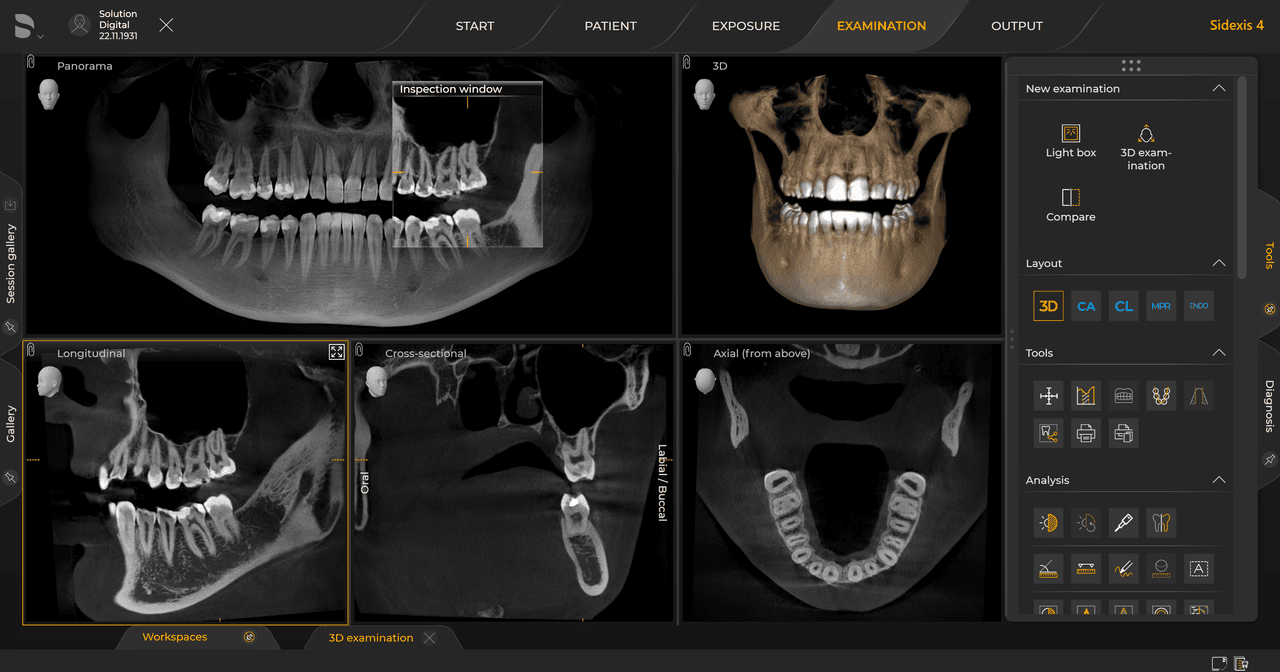

Con el modo de dosis baja inteligente 3D, obtiene imágenes 3D en el rango de dosis de una imagen radiológica 2D. En el modo HD (hasta 1400), las imágenes individuales se obtienen durante una única rotación y se convierten en un volumen 3D con hasta 80 μm para imágenes de bajo ruido en alta resolución.

Las unidades de radiología de Dentsply Sirona funcionan exclusivamente con Sidexis 4. Sin embargo, la migración de datos de Sidexis XG a Sidexis 4 es muy fácil. Sidexis 4 permite una experiencia digital completa con las últimas herramientas